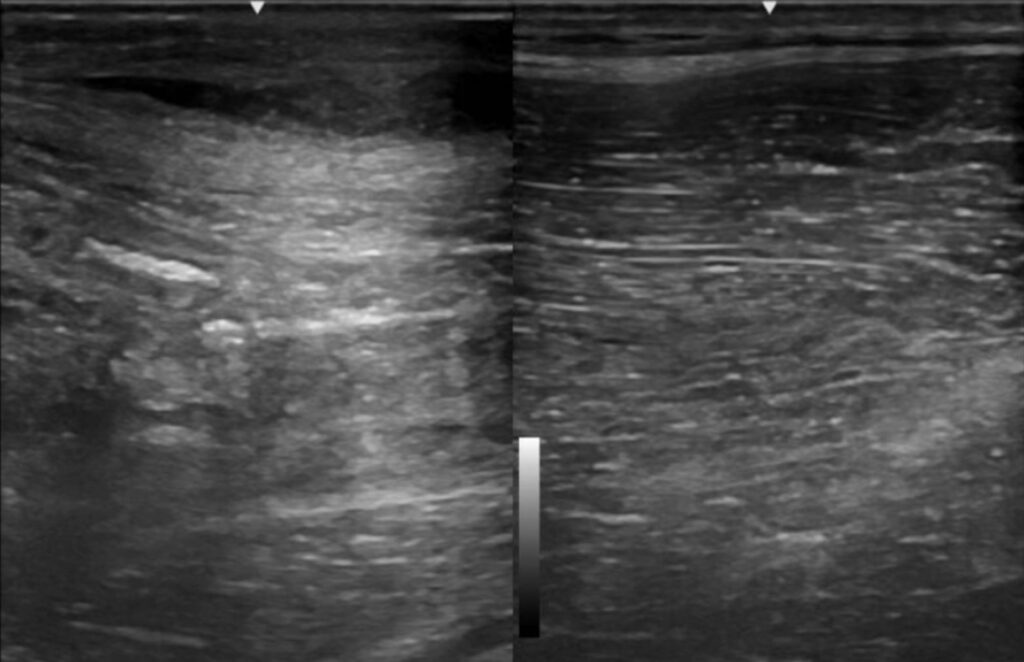

When in doubt, said Deacon, remember the horse has two sides: “An abnormality might be more apparent when comparing it to the normal opposite side.”

Once you’ve mapped out the normal structures on ultrasound, move on to what you don’t know, she said. Characterize the mass ultrasonographically using size (measurements of length, width, and depth of the mass to check progress over time), shape, margins, and echogenicity.

To determine the shape of the mass, rotate your ultrasound transducer on the structure of interest (e.g., orthogonal views). “This can help confirm if the mass is spherical versus tubular in shape.”

“The character of the mass or swelling contents is a critical piece of information that will help you narrow down your list of differentials,” said Deacon. “Pay attention to whether it’s homogenous vs. heterogenous, anechoic/hypoechoic/hyperechoic, solid vs. fluid. Color flow doppler can be used to assess for blood flow within the structure, which is particularly important for things like neoplastic masses or a vessel bleeding into a hematoma.”